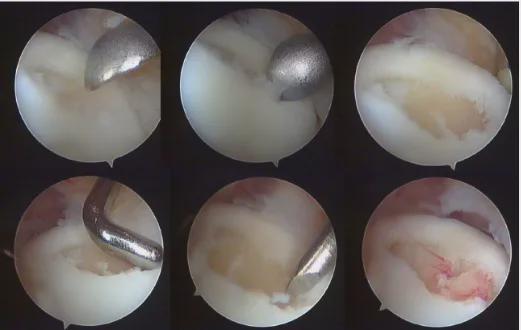

- 病灶小(<8mm),损伤2、3级,可通过:骨髓刺激技术:微骨折/逆向钻孔治疗(图3、图4)

图3关节镜下微骨折治疗距骨骨软骨损伤

手术治疗可以切开或关节镜下手术,我科通常选用关节镜下检查病变情况,儿童青少年病变程度不严重多采用镜下微骨折或钻孔手术。